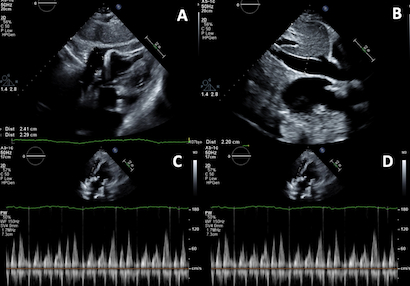

A 68-year-old woman, one month after bioprosthetic mitral valve replacement for severe mitral regurgitation, presented with fatigue and mild dyspnea on exertion. She was hypotensive and tachycardic, with pulsus paradoxus on exam. Transthoracic echocardiogram revealed a small anterior pericardial effusion and echocardiographic features consistent with tamponade physiology. A large right-sided pleural effusion was also discovered on CT imaging. She underwent urgent thoracentesis, after which tamponade findings resolved, and her symptoms markedly improved without pericardiocentesis.

This case highlights an uncommon but clinically significant cause of tamponade physiology: extracardiac compression from a large pleural effusion. While tamponade is usually due to pericardial fluid, elevated intrathoracic pressure from a pleural effusion can similarly impair diastolic filling and cause classic tamponade. The presence of a small pericardial effusion initially raised concern for being the primary etiology of tamponade, but resolution of symptoms and echocardiographic findings after thoracentesis clarified the source. This underscores the importance of considering alternative causes of tamponade physiology, particularly in postoperative cardiac patients with pleural effusion. Echocardiographic signs of tamponade are not specific to pericardial effusion; thus, clinical correlation and comprehensive imaging are essential to determine the true etiology. Timely recognition of pleural effusion-induced tamponade enables effective stabilization through a less invasive intervention and obviates unnecessary invasive cardiovascular procedures.